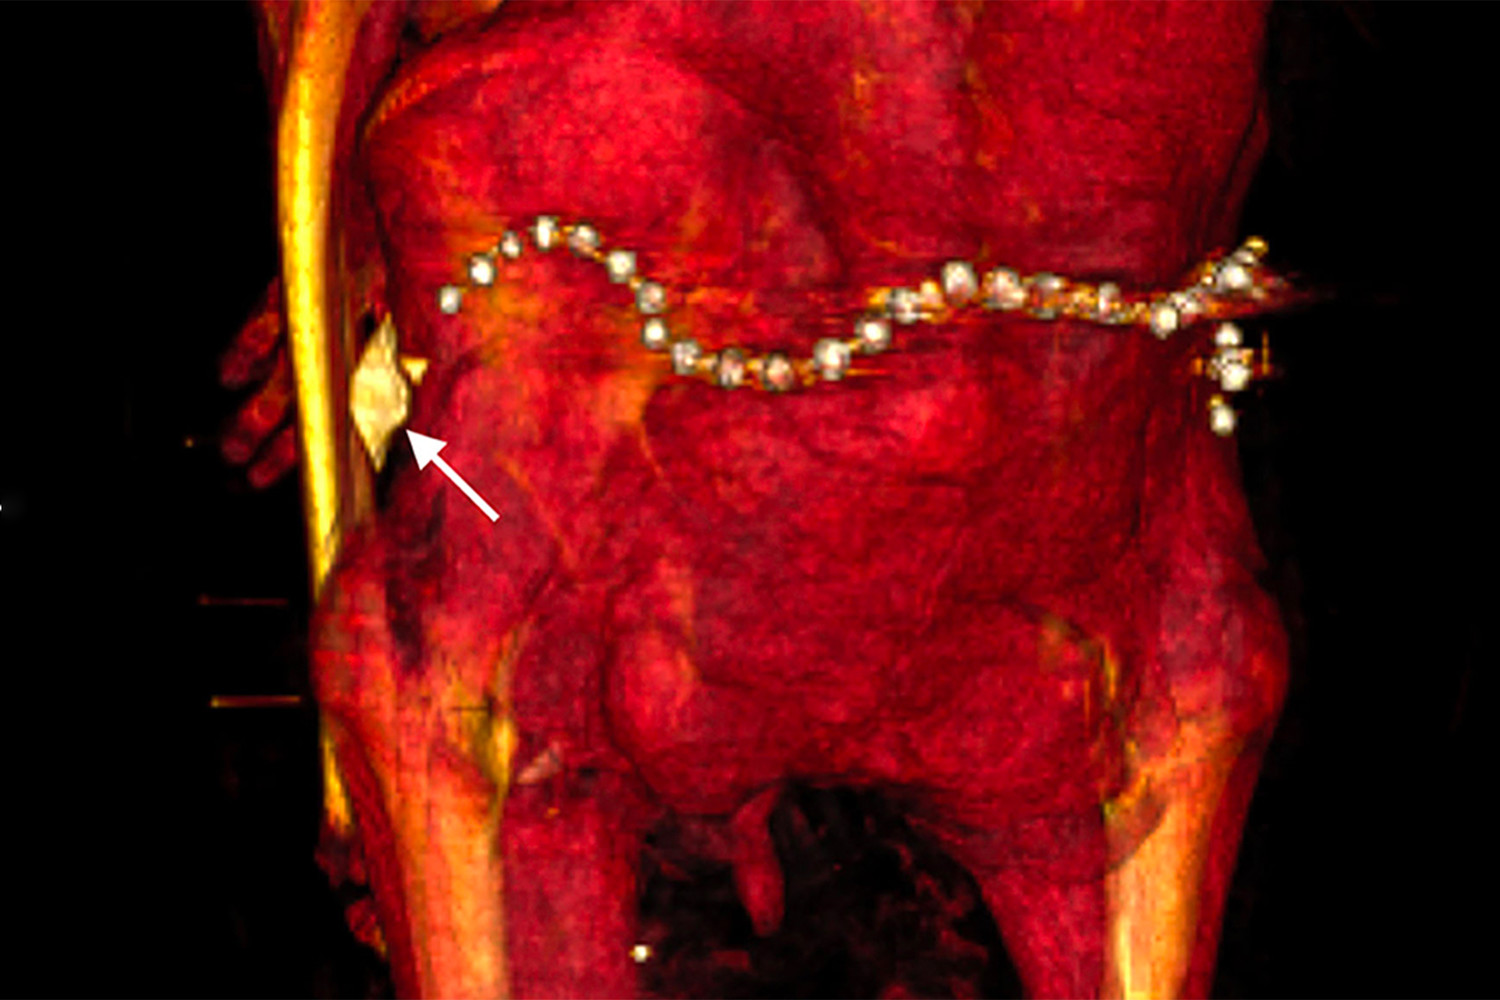

В бинтах исследователи также обнаружили около 30 украшений, в частности пояс из металлических (вероятно, золотых) бусин в задней части тазовой области, и фаянсовый амулет в форме раковины улитки у левого бедра.

При повторном захоронении мумию явно пытались «отремонтировать» — пропитанные смолой бинты фиксировали оторвавшуюся из-за перелома шейных позвонков голову, прикрывали повреждения брюшной полости. Сломанным и вывихнутым конечностям придано подходящее положение. Ступни зафиксированы с помощью деревянных дощечек.